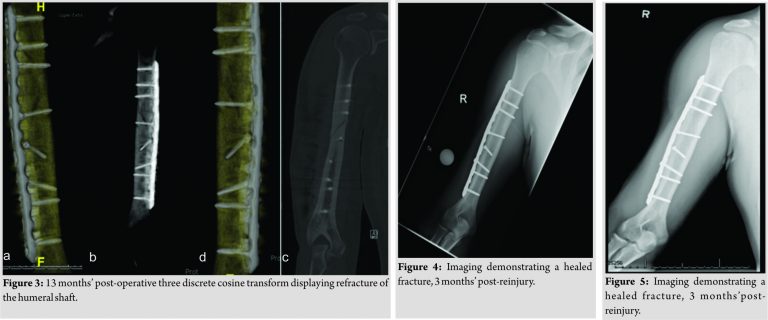

Six weeks following the surgery, the patient began to jog and lightly throw a baseball. He began light weight lifting and continued home PT to strengthen the elbow and shoulder. By 3 months’ post-operative, the fracture had united. The patient returned to college baseball 6 months postoperatively. Eleven months following the fracture repair and 5 months following return to baseball, the patient felt a “pop” with immediate pain in the posterolateral aspect of his right arm following a throw. Radiographs of the right humerus revealed two new fracture lines. A computed tomography scan confirmed anew spiral fracture of the midshaft of the humerus extending from the second proximal screw to the lag screw. The hardware remains intact, and there is no evidence of hardware failure or loosening (Fig. 3). Vitamin D levels were obtained and were found to be low. The patient’s 25-OH Vitamin D level was found to be 24.3 ng/mL, while the reference range was 32.0–100.0 ng/mL. His serum calcium was within normal limits, at 9.5 ng/mL. In addition, a thyroid function panel was within normal limits. The thyroid panel was obtained, to rule out hyperthyroidism, as this can lead to secondary osteoporosis. The patient was, therefore, started on Vitamin D, given a one-time dose of 50,000 U followed by 2000 U daily. The patient was placed in a sling, for 1 month, following refracture. The patient began physical therapy 3 weeks following the refracture. Initial therapy consisted of numerous stretching activities in addition to using resistance bands for shoulder and elbow range of motion exercises. Throughout the recovery process, he attended therapy 3 times a week. The patient had full shoulder and elbow range of motion at 4 weeks’post-refracture. At 3 months’post-reinjury, the fracture appeared to be healed (Fig. 4). He was cleared for light sporting activities at 3-month post-reinjury. At this time point, the patient began throwing exercises at this time with the collegiate baseball athletic trainer. He began performing four sets of 10 throws, from a distance of 60 feet. The intensity of throwing at this time was 50% of full strength. He performed throwing exercises 3 days a week. After 2 weeks of these throwing exercises, he began six sets of 10 throws with each set having an increase of intensity by 5–10%, where he had perform his last set at 85% of maximum throwing strength. 2 weeks into his therapy, he also began to perform the following weight training, in three sets of 10 repetitions: Seated rows, lat pull downs, and tricep extensions. The patient continued to exercise and work with the college’s athletic trainer. After 3 months of working with physical therapy and the collegiate athletic trainer and at 6 months following re-injury, he was back to throwing at 100% intensity. He gradually increased throwing distance and weight training over 4 months of therapy. He continues to take 2000 U of Vitamin D3, once a day. Today, he is 1 year out from the recurrent stress fracture and is throwing a baseball at 145 feet with original pre-injury intensity. He finished his senior year of college back on the baseball field, as his teams start catcher. Imaging of his humerus at 1 year post-recurrent stress fracture is demonstrated in (Fig. 5).